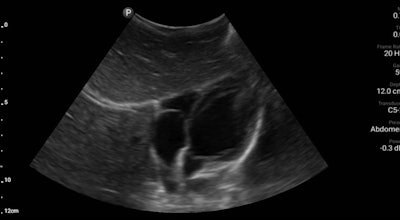

The team also saw several children with high blood pressure and heart rate. The children underwent physical examination with additional ultrasound exams that revealed normal-appearing cardiac activity with no evidence of pulmonary hypertension. Another patient was a pregnant woman with occasional abdominal pain. The woman, who lived a two- to three-day walk from the closest hospital, received fetal sonography and was reassured that the fetus was developing as expected.